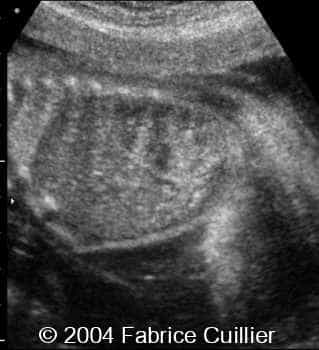

Multicystic kidney disease, unilateral, in a twin

This is a case of unilateral multicystic kidney disease in a twin with no other anomalies.